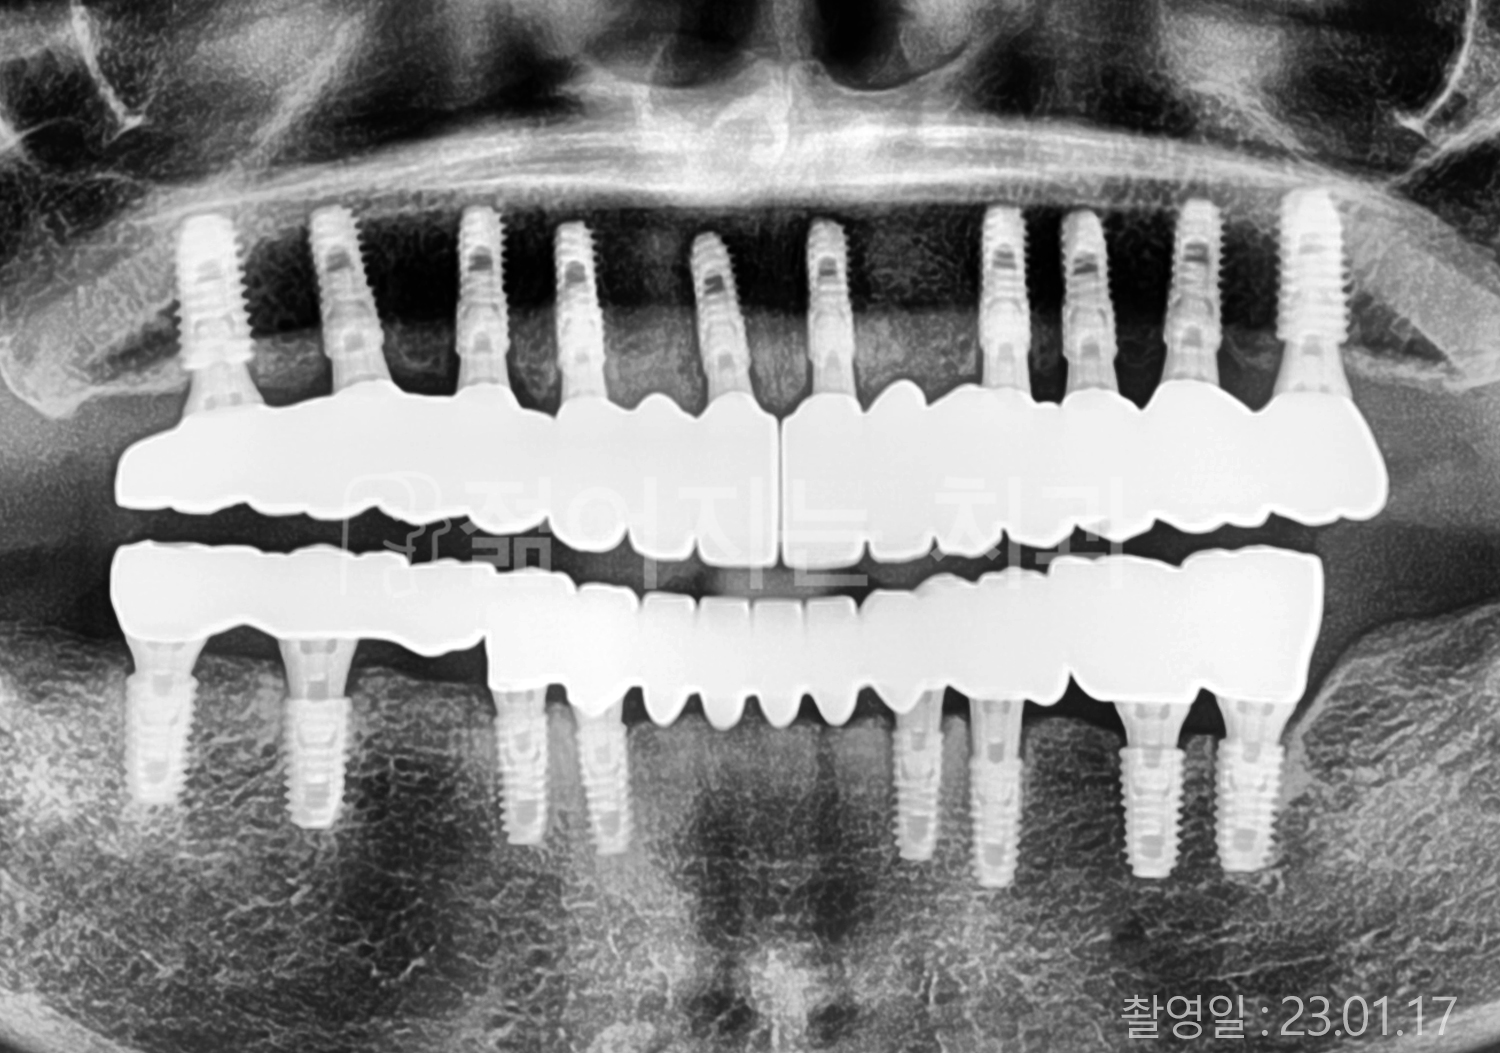

• 60대 전체치아 10개 이상 임플란트